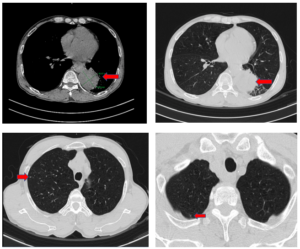

CASE LÂM SÀNG: VAI TRÒ CỦA PET/CT TRONG ĐÁNH GIÁ GIAI ĐOẠN TRƯỚC ĐIỀU TRỊ Ở BỆNH NHÂN UNG THƯ PHỔI TẠI TRUNG TÂM YHHN VÀ UNG BƯỚU BỆNH VIỆN BẠCH MAI

CASE LÂM SÀNG: VAI TRÒ CỦA PET/CT TRONG ĐÁNH GIÁ GIAI ĐOẠN TRƯỚC ĐIỀU TRỊ Ở BỆNH NHÂN UNG THƯ PHỔI TẠI TRUNG TÂM YHHN VÀ UNG BƯỚU BỆNH VIỆN BẠCH MAI GS.TS. Mai Trọng Khoa, PGS.TS. Phạm Cẩm Phương, BS. Lê Viết Nam, BSNT Mai Thị Chung. Trung...